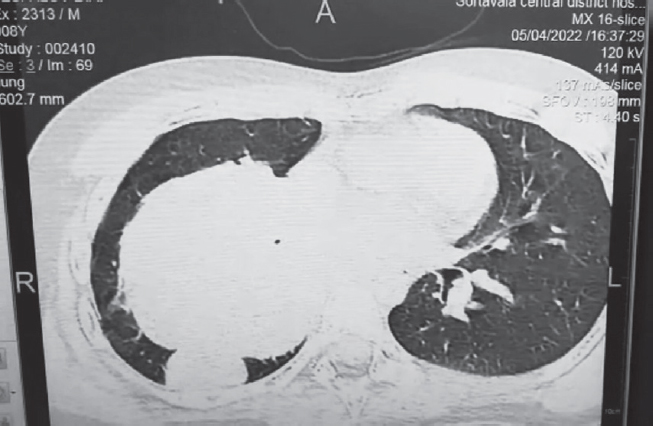

На момент госпитализации болен, со слов родителей, 10 дней. Начало заболевания — покашливание, умеренная астения. Осмотрен педиатром по месту жительства, состояние расценено как течение острой респираторной вирусной инфекции, назначена симптоматическая терапия Амброгексалом. На фоне лечения — без улучшения, отмечается повышение температуры до 38 °C, кашель, в связи с чем ребенка повторно осматривал участковый педиатр, коррекция терапии не проводится. Мама самостоятельно начала давать мальчику Амоксиклав. На 2-й день приема антибиотика, со слов родителей, отмечалось улучшение самочувствия, нормализация температуры тела, уменьшение кашля. Семья уехала на отдых в Карелию, где на 3-й день пребывания у ребенка наблюдается резкое ухудшение состояния в виде выраженной одышки, отказа от еды и питья, слабости. С данными жалобами ребенок госпитализирован в ГБУЗ РК «Сортавальская ЦРБ». Состояние при поступлении расценено как тяжелое. Мальчик вялый, адинамичный. При осмотре отмечается бледность кожных покровов, одышка смешанного характера до 40–46 дыханий в минуту, SpO2 90 %. Зев без катаральных явлений. Периферические лимфоузлы не увеличены. Носовое дыхание свободное. Аускультативно в легких: справа ослабленное дыхание, сухие свистящие хрипы по всем легочным полям. Перкуторно над легкими: укорочение легочного тона справа в проекции средней доли. Тоны сердца ясные, ритмичные, 102 в минуту. Артериальное давление 95/60 мм рт. ст. Живот мягкий, безболезненный, печень по краю реберной дуги, селезенка не пальпируется. Физиологические отправления в норме. В клиническом анализе крови при поступлении гемоглобин 119 г/л, эритроциты 4,48 · 1012/л, лейкоциты 6,68 · 109/л, тромбоциты 336 · 109/л, палочкоядерные нейтрофилы 5 %, сегментоядерные нейтрофилы 85 %, лимфоциты 6 %, моноциты 4 %. В биохимическом анализе крови: общий белок 66,7 г/л, С-реактивный белок 33,7 ед., аланинаминотрансфераза 14,7 U/I, аспартатаминотрансфераза 28,0 U/I, билирубин общий 5,3 ммоль/л, глюкоза 7,52 ммоль/л, мочевина 5,0 ммоль/л, креатинин 23 ммоль/л. Общий анализ мочи: лейкоциты 20–22 в поле зрения, эритроциты 25–27 в поле зрения. Коагулограмма: Д-димер 3,27. На рентгенограмме легких (прямая и правая боковая проекция, рис. 1) и СКТ легких (рис. 2) — справа, в проекции SVI, огромное образование с ровными и четкими контурами, плотной интенсивности, не сопровождающееся нарушением проходимости бронхов.

Рис. 2. Пациент, 8 лет. Компьютерная томограмма, легочный режим: А (аксиальная проекция) — большое солидное образование в 6-м сегменте правого легкого